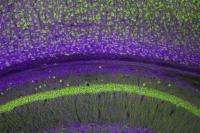

Terobosan baru dalam dunia neurosains menunjukkan bahwa ilmuwan kini mampu “mengedit” sirkuit otak untuk memperkuat memori